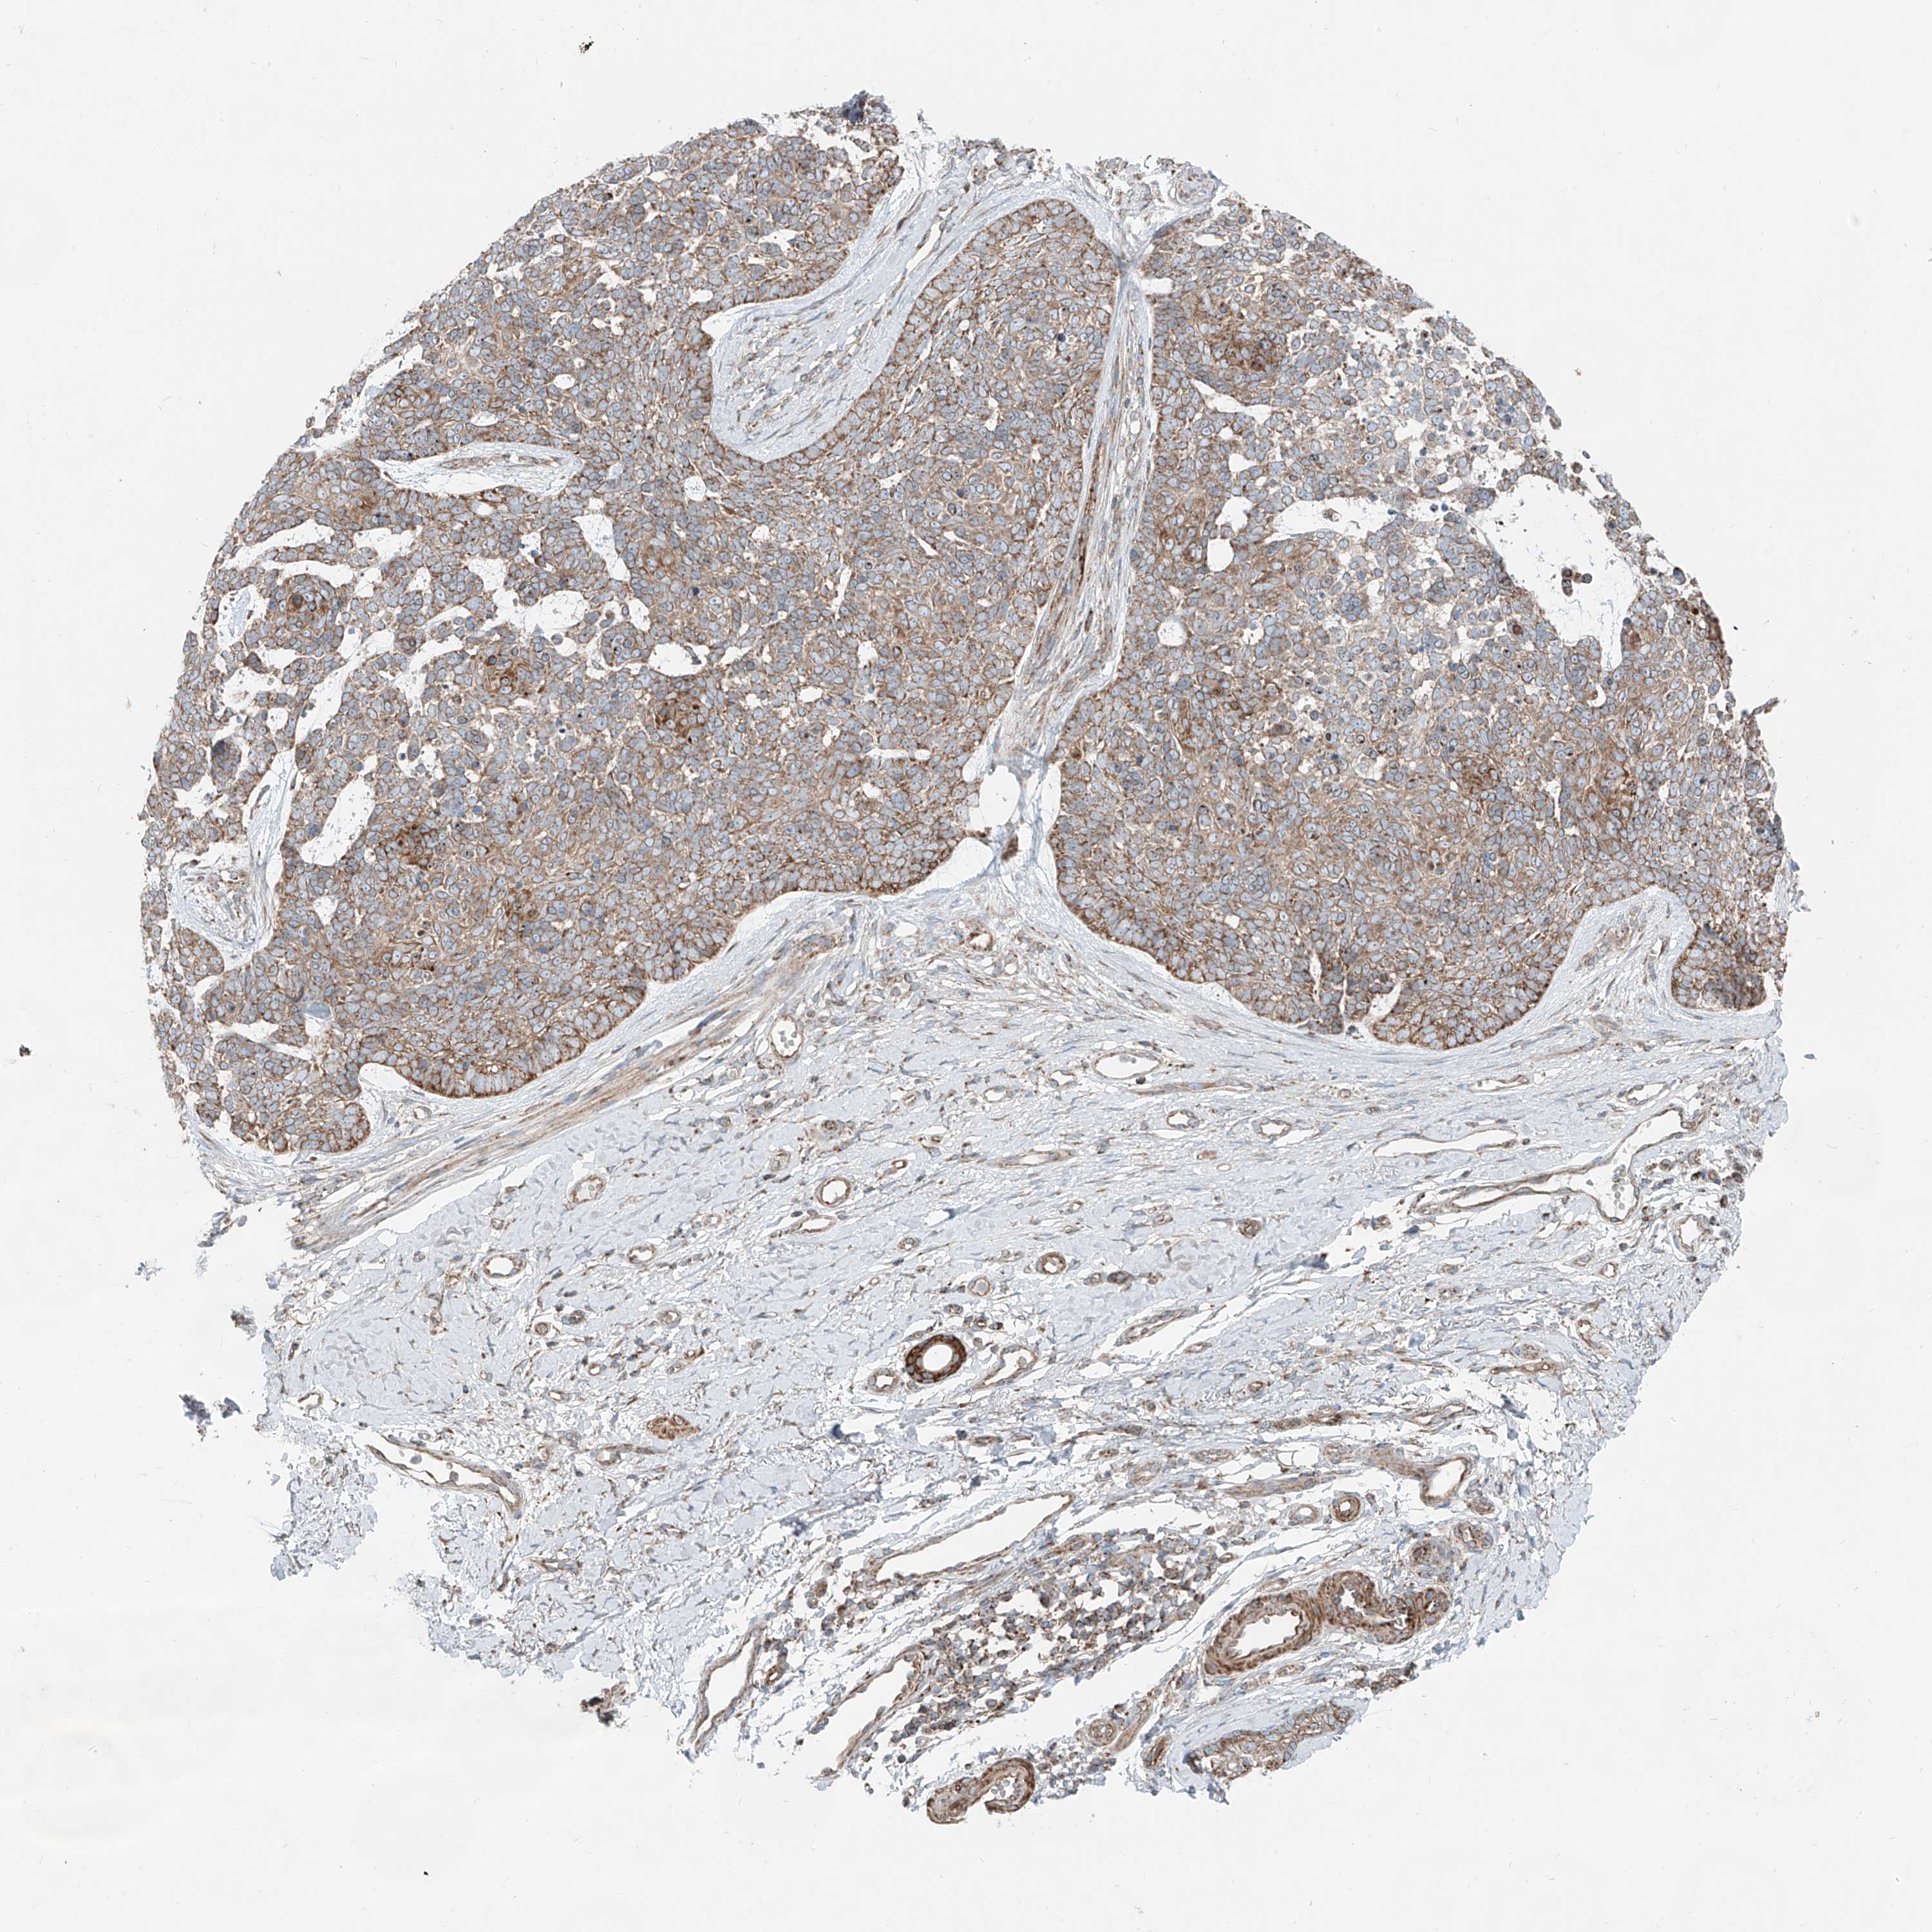

SKIN CANCER - Protein expressioni

A mouse-over function shows sample information and annotation data. Click on an image to view it in a full screen mode. Samples can be filtered based on level of antibody staining by selecting one or several of the following categories: high, medium, low and not detected. The assay and annotation is described here.

Antibody stainingi

Antibody staining in the annotated cell types in the current human tissue is reported as not detected, low, medium, or high, based on conventional immunohistochemistry profiling in selected tissues. This score is based on the combination of the staining intensity and fraction of stained cells.

Each image is clickable and will lead to virtual microscopy that enables deeper exploration of all samples and also displays staining intensity scores, fraction scores and subcellular localization as well as patient and tissue information for each sample.

Antibody HPA030316

Staining

High

Medium

Low

Not detected

Intensity

Strong

Moderate

Weak

Negative

Quantity

>75%

75%-25%

<25%

None

Location

Nuclear

Cytoplasmic/membranous

Cytoplasmic/membranous,nuclear

Squamous cell carcinoma, NOS